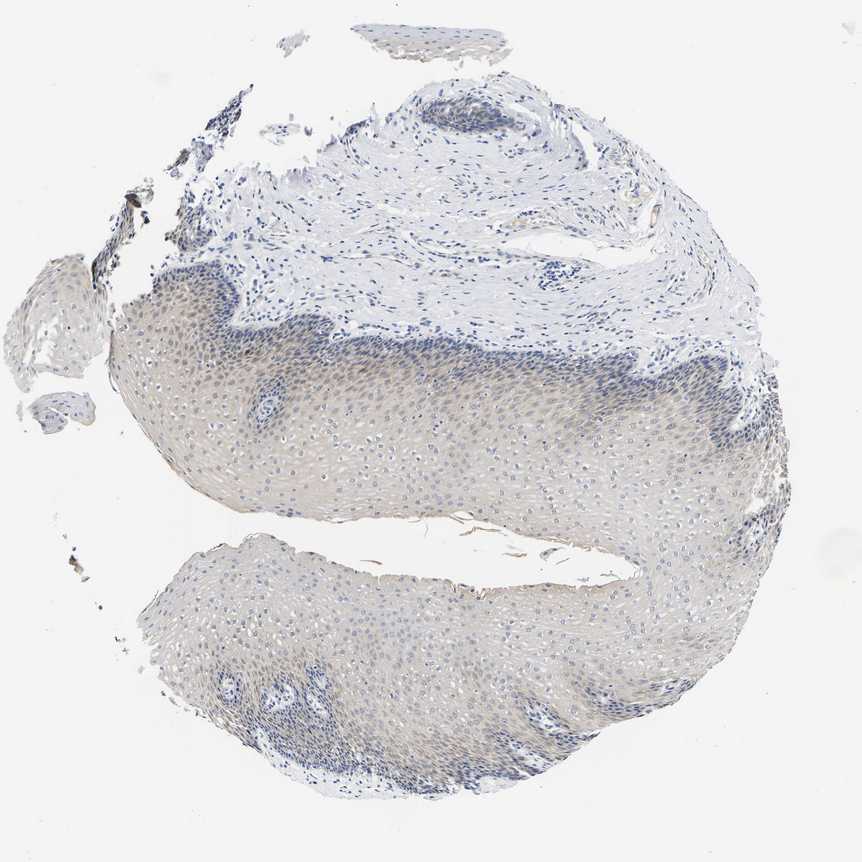

ESOPHAGUS - Antibody stainingi

Antibody staining in the annotated cell types in the current human tissue is reported as not detected, low, medium, or high, based on conventional immunohistochemistry profiling in selected tissues. This score is based on the combination of the staining intensity and fraction of stained cells.

Each image is clickable and will lead to virtual microscopy that enables deeper exploration of all samples and also displays staining intensity scores, fraction scores and subcellular localization as well as patient and tissue information for each sample.

Antibody HPA019049Antibody HPA019051

Squamous epithelial cells Not detectedMedium